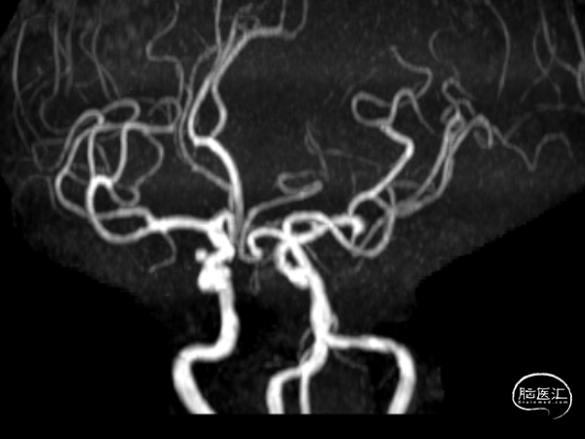

头颅MRA

头颅MRI+MRA提示

脑血管造影

3D-DSA检查